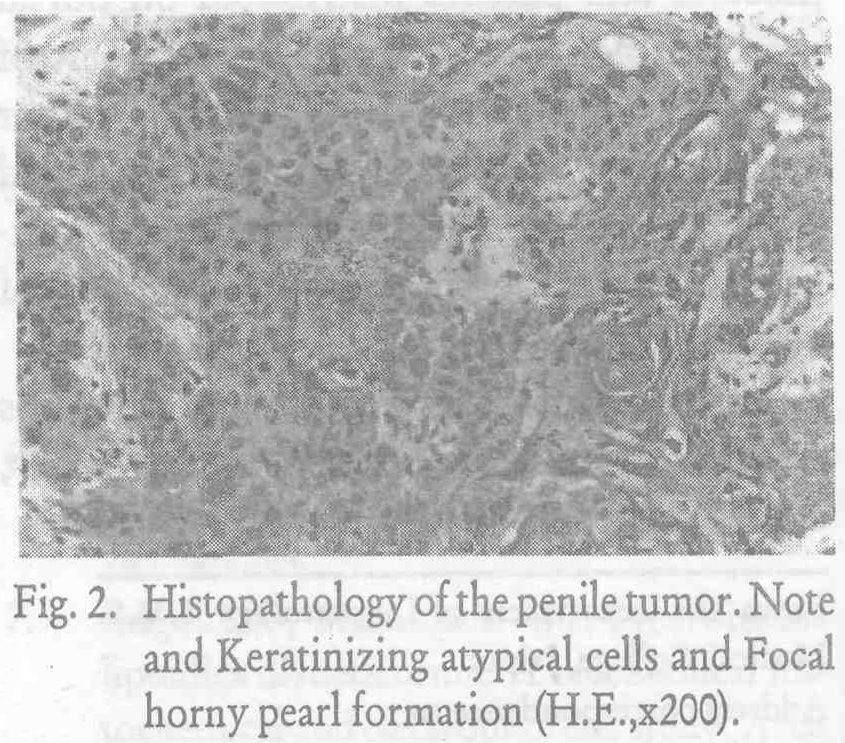

penile cancer photos download

Posts: penile cancer photos download